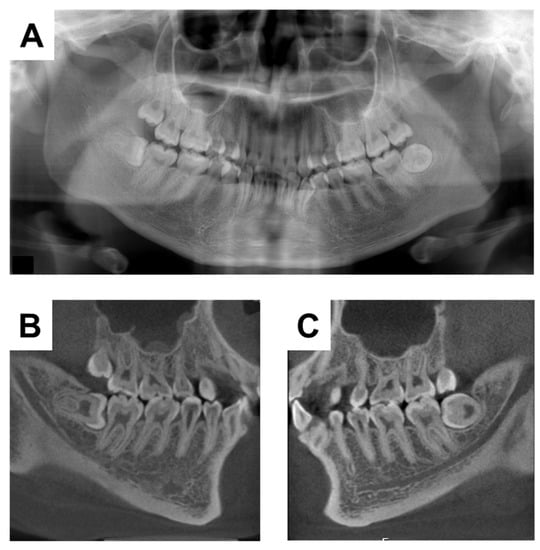

2. Case Presentation